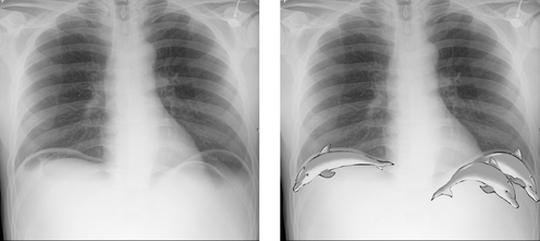

🐬The leaping dolphin sign 🐬 This sign was first described by Cho and Baker on supine abdominal films where intraperitoneal gas would highlight different slips of muscle in the diaphragm, thus giving arcuate lucencies which converged superomedially and resembled leaping dolphins. This can also be seen occasionally on erect films, either CXR or AXR. Other marking signs of pneumoperitoneum are:🗝️🗝️🗝️ 1.Rigler's sign (gas outlining both sides of bowel) 2.the triangle sign (the angulation can only occur when the gas is outside the wall) 3.hyperlucent liver (due to overlying gas) 4.anterior superior oval sign (gas locules projected over the liver) 5.ligamentum teres and falciform ligament signs (gas outlining the respective ligaments) 6.the hepatic edge sign (gas locules on the inferior surface of the liver) 7. The football sign (oval lucency due to collection of a large amount of gas anteriorly on a supine radiograph).